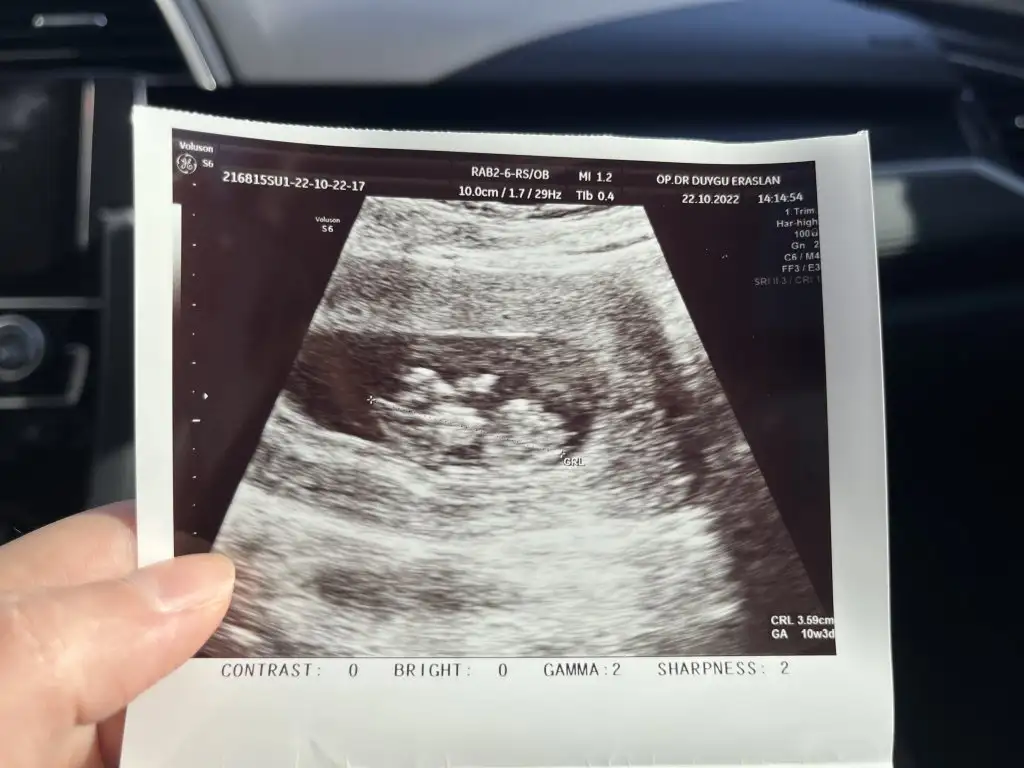

Merhaba bebeğim 10 haftalık. Benim içinde yorum yapar mısınız. teşekkürler <3Selam Kızlarbir çok kişi gruplardan beni bilir. Yine yetiştim imdatlara

Buda usg lerimSelam Kızlarbir çok kişi gruplardan beni bilir. Yine yetiştim imdatlara